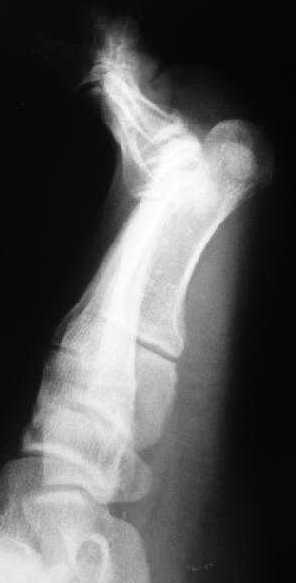

Та же проблема - по крайней мере на снимке в аппарате (фас) отчетливо видно перелом ее головки.

3 кстати, Вы перелом пкрвой плюсневой видите? В каком месте и на каком снимке?

Вот головка более прицельно.

Вот теперь вижу :)

предлагаю. Все то же самое плюс по обстоятельствам, в зависимости от внутриоперационных находок- либо ничего не делаем, либо фиксируем фрагмент спицей ( можно даже адсорбируемой - получим пласмассоостеосинтез:)) или микрошурупом, либо - если вправление пойдет совсем плохо - все же как минимум восьмая неделя - эксцизионная пластика сустава .

Вторую плюсневую вправлять и фиксировать спицей.